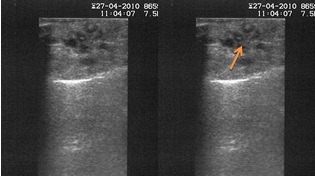

- על-שמע (אולטרסאונד) רגיל, ואולטרסאונד אנדוסקופי (EUS):בדיקת הסונר הרגיל פחות טובה לזיהוי של נגעים קטנים בלבלב אבל בהחלט רגישה לזיהוי נגעים ציסטים (תצלום 29.9). האולטרה האנדוסקופי שיפר בהרבה את יכולת הסונר לזהות נגעים בלבלב.